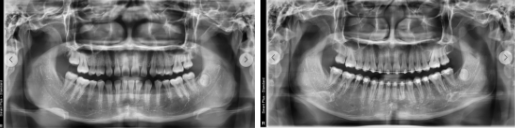

부정교합 치료 전후 파노라마 X-ray(엑스레이)

초진에서는 파노라마 엑스레이와 구강 상태 확인 후 대략적인 치료 방향을 안내받고, 정밀검사에서 자세한 기록을 만들어 치료 계획을 확정합니다.

처음 방문하는 초진에서는 치아와 턱 주변을 넓게 촬영하는 파노라마 엑스레이와 구강 상태 확인을 통해,

교정적으로 어떤 문제가 있는지 파악하고 대략적인 치료 방법을 설명드립니다.

이 검사 자료를 바탕으로 엑스레이와 모형을 분석해 문제점을 정리하고, 개인에게 맞는 치료 계획을 상담을 통해 안내하게 됩니다.

교합평면 변화 비교 자료